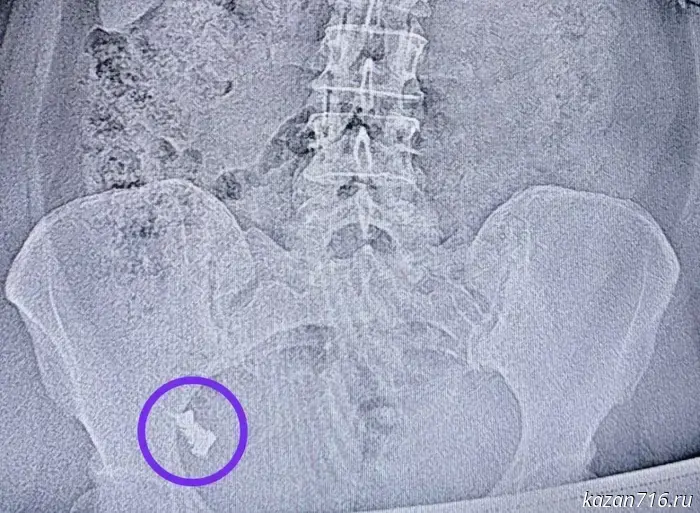

Doctors at the Republican Clinical Hospital of Tatarstan removed a denture from a woman's intestine that she had swallowed.

Doctors at the Republican Clinical Hospital saved a woman who accidentally swallowed her dental prosthesis. The clinic's press service reported this.

A 50-year-old resident of Kazan accidentally swallowed her dental prosthesis. She repeatedly refused an esophagogastroduodenoscopy (EGD) as well as hospitalization, claiming the prosthesis would pass on its own.

A week later the woman was admitted to Surgical Department No. 1 because the prosthesis had become stuck at the junction of the small and large intestine.

Endoscopist Nail Iskhakov removed the prosthesis during a colonoscopy. The procedure was performed under the supervision of anesthesiologist-resuscitator Elena Chuenkova, since the prosthesis was already in a hard-to-reach location. With anesthesia, the removal was painless.

Photo: RCH press service